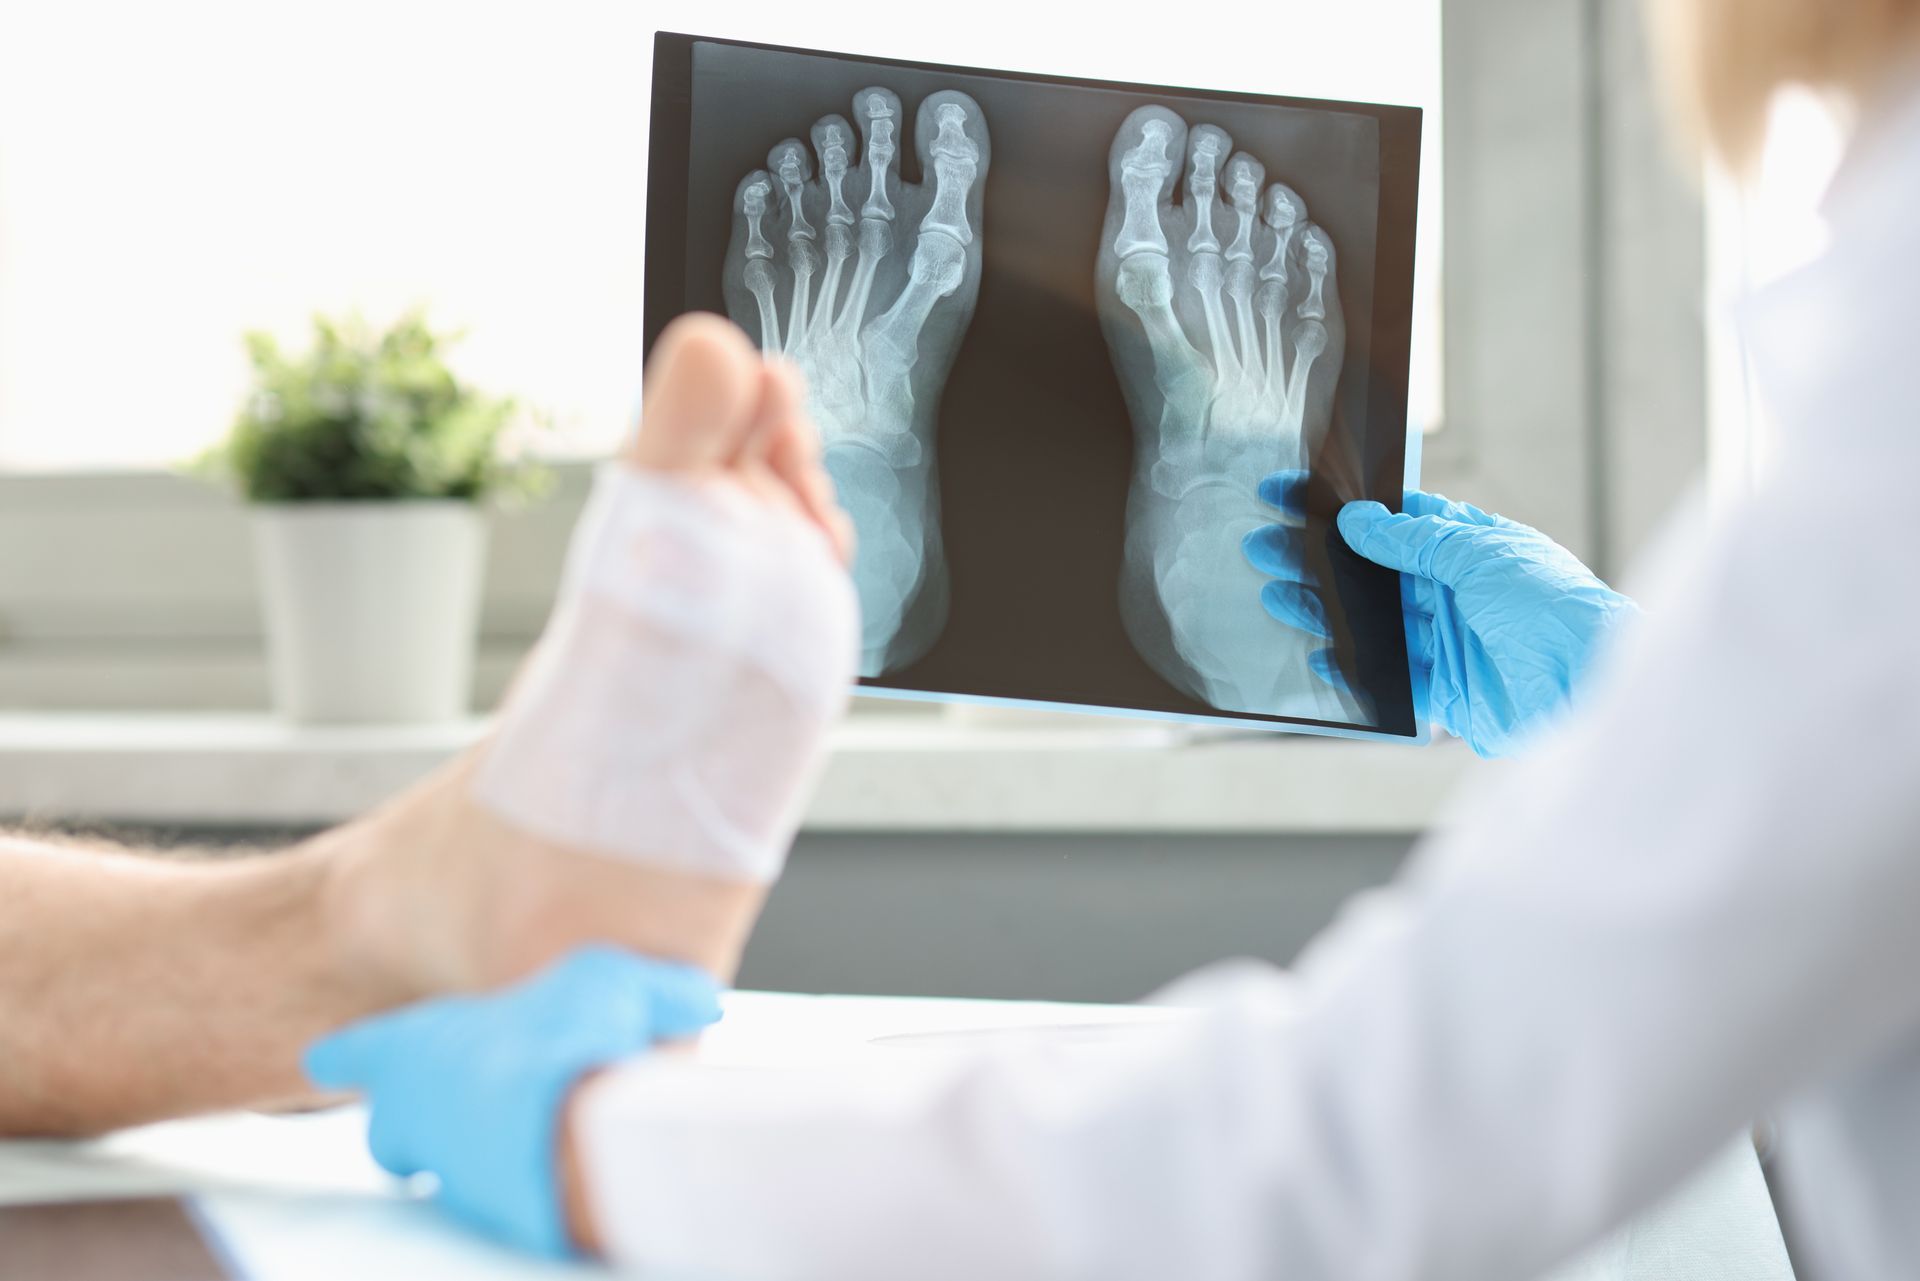

Powerful Solutions for Foot Pain

Foot pain takes many forms, and recognizing the cause is key to effective treatment. Common conditions include bunions, hammertoes, ingrown nails, fungal infections, corns, calluses, stress fractures, and neuropathies.

Common Causes and Conditions

• Bunions and hammertoes resulting from structural imbalances and pressure.

• Ingrown nails and fungal infections impacting skin and nail health.

• Stress fractures caused by overuse or trauma.

• Neuropathy linked to diabetic or nerve conditions.

• Infections and inflammation from injury.

Non-surgical Treatment Options

We prioritize treatments like physical therapy, bracing, orthotics, medication, and lifestyle strategies to relieve foot pain effectively. Our custom orthotics correct mechanical issues, while laser therapy treats stubborn infections. Patient education helps prevent recurrence.